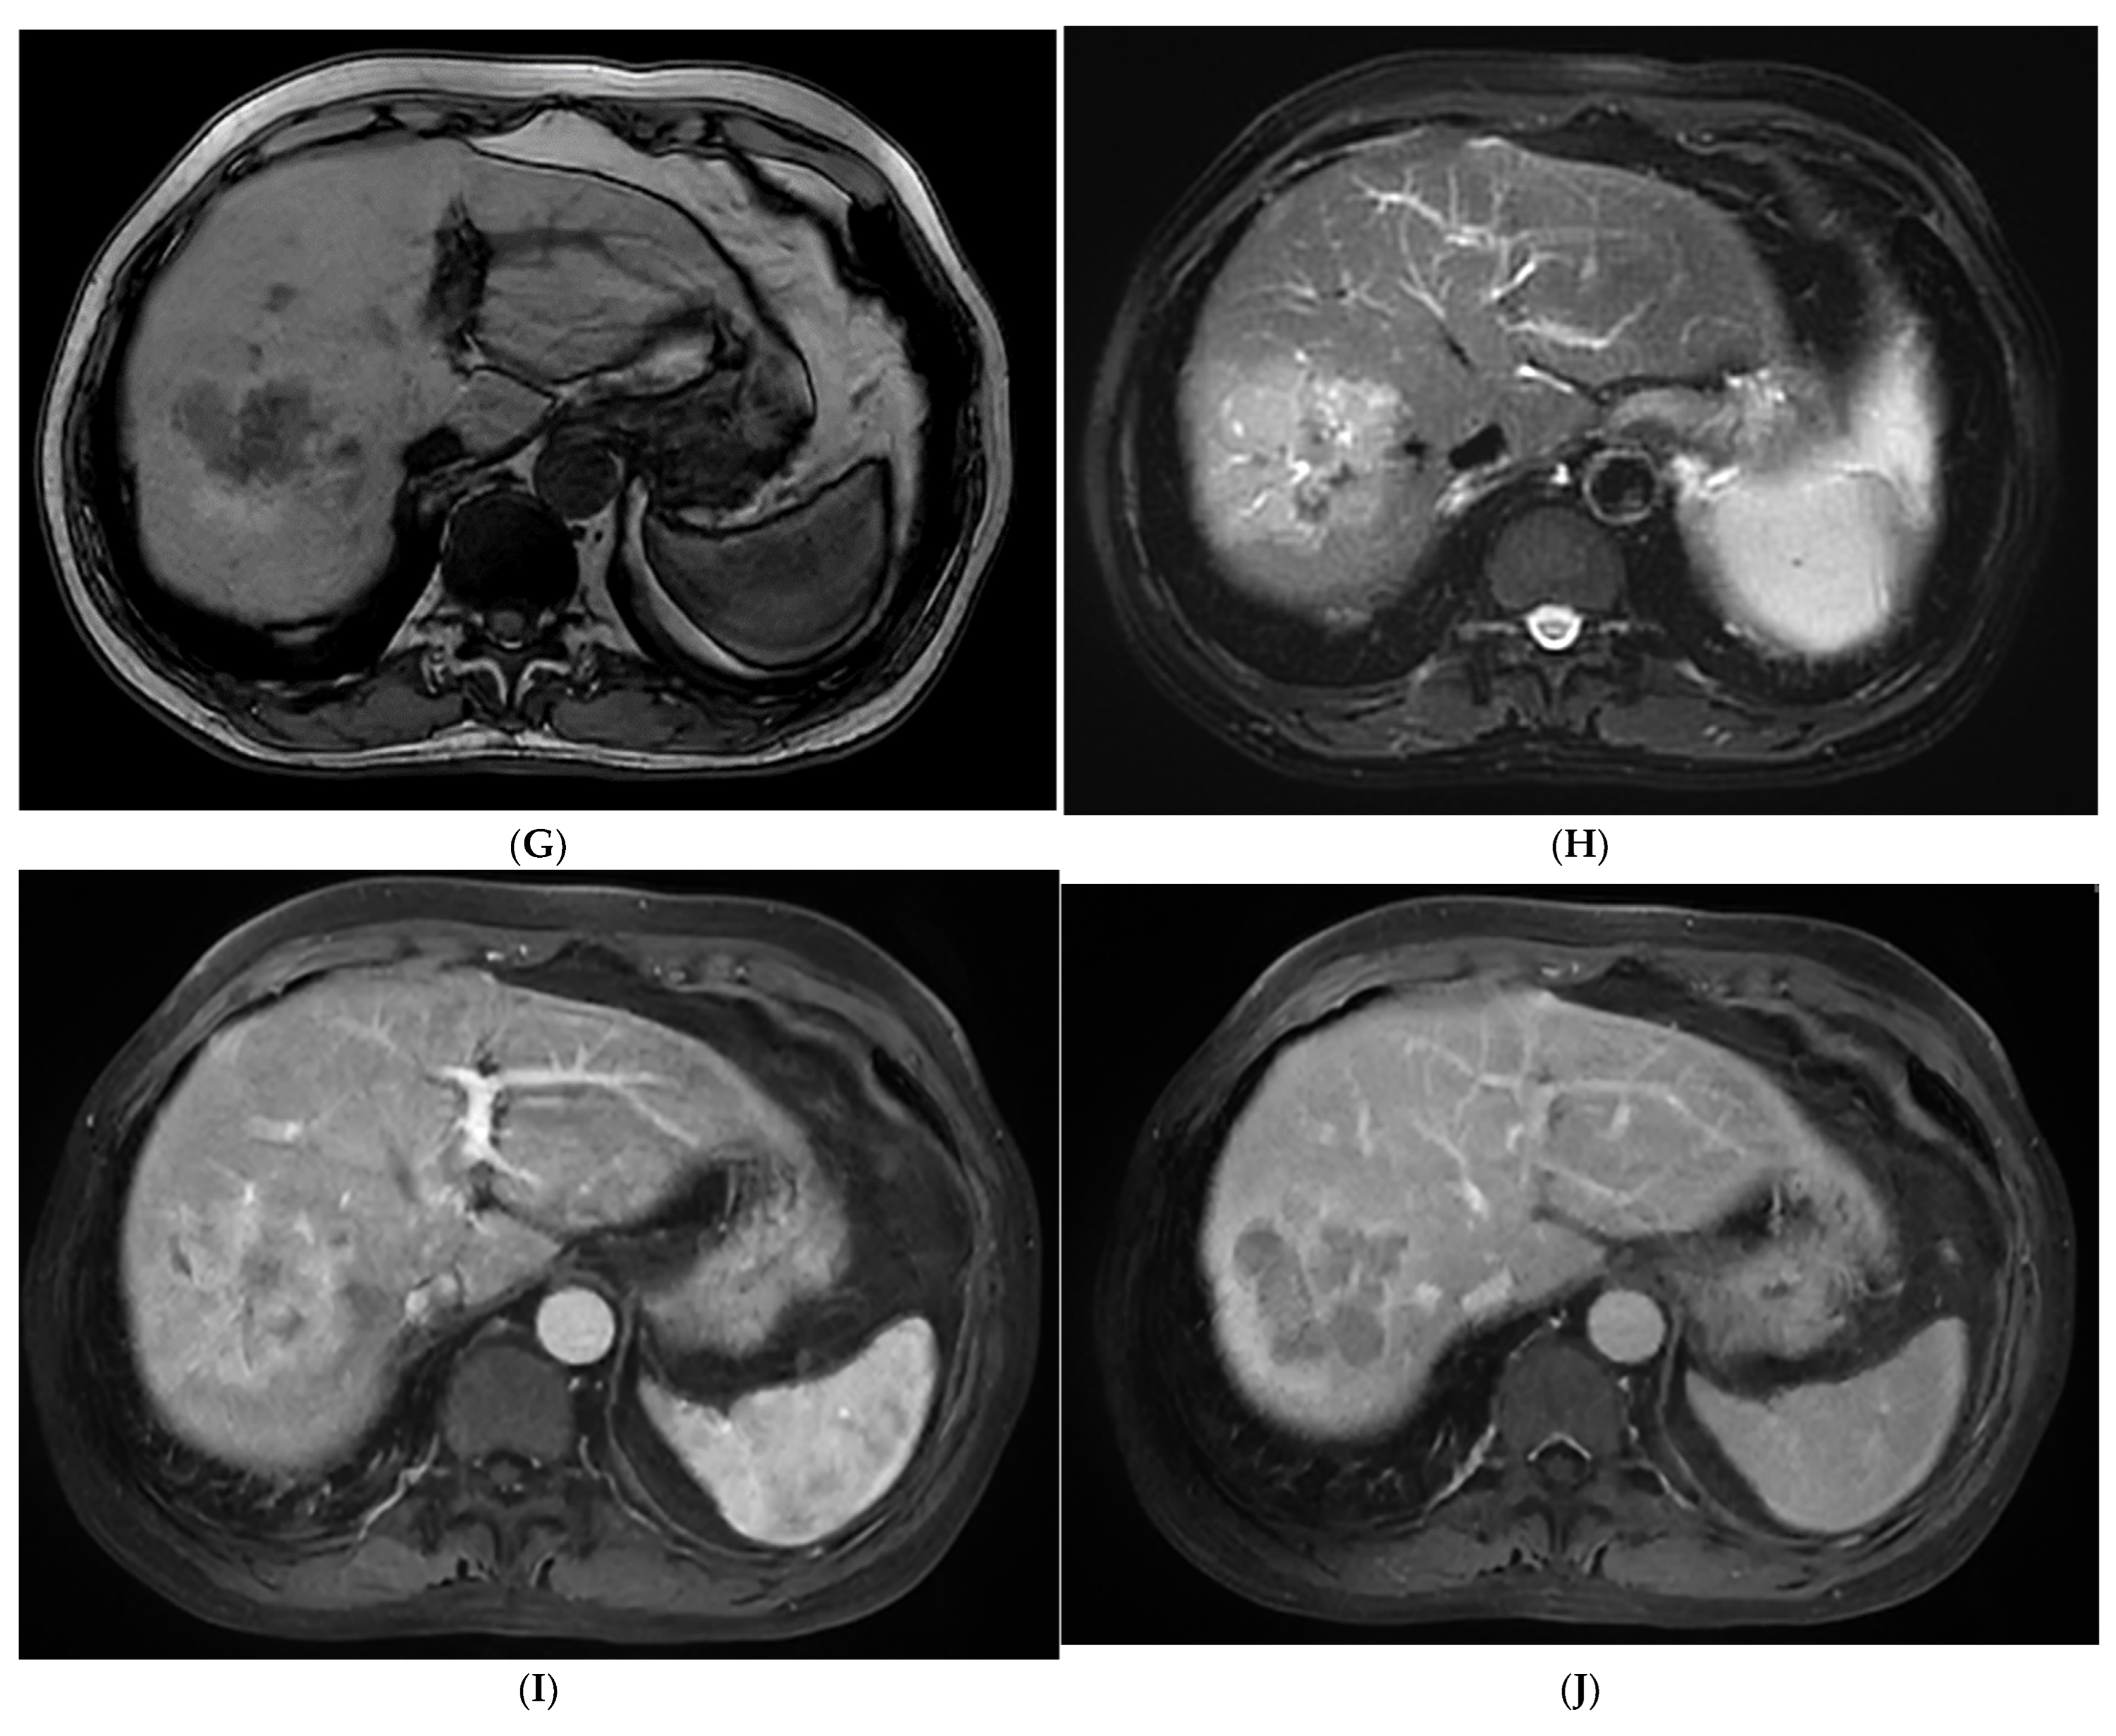

3.3. CEMRI Features

As shown in Table 3, SH-HCCs mainly showed hypo-intensity on T1WI and hyperintensity on T2WI, and there were no significant differences between the two groups (p > 0.05). However, there was a signal drop in the T1WI opposed-phase which was observed in 84.6% of SH-HCCs, which was much higher than for the non-SH-HCCs (p = 0.000). As seen via a contrast-enhanced scan, most SH-HCCs and non-SH-HCCs exhibited heterogeneous hyperenhancement in the arterial phase (80.8% versus 69.2%, p = 0.337). During the delayed phase, 76.9% (20/26) of SH-HCCs and 88.5% (23/26) of non-SH-HCCs exhibited hypo-enhancement (p = 0.264). As a result, SH-HCCs and non-SH-HCCs were mostly classified into LR-4 or LR-5. Notably, diffuse fat in mass was detected in 57.7% (15/26) SH-HCC lesions, which was significantly higher than for non-SH-HCCs (p < 0.001). Hemorrhage and necrosis in mass were of similar frequency in the two groups (p = 0.350, p = 0.703, respectively). The contrast-enhanced images of SH-HCC are shown in Figure 1, and images of non-SH-HCC are displayed in Figure 2.

In the present study, the MRI characteristics of SH-HCCs were also fully analyzed. The most notable result was that a signal drop was observed in 84.6% of SH-HCCs in the T1WI opposed-phase compared with the in-phase. In addition, a diffuse fat change in mass was seen in 57.7% of SH-HCCs. Our results were in line with Inui et al. [13]. As seen via contrast-enhanced scan, even though 88.5% of SH-HCCs showed hyperintensity in the arterial phase, the remaining 7.7% of these lesions exhibited hypo-intensity. Hypovascular enhancement is characteristic of the progressed HCCs but not for early, fatty degeneration or well-differentiated HCCs [29,38]. That is to say, the fact that they are fat-containing coincides with the presence of enhancement intensity during the arterial phase, and the SH-HCCs with a dominant fat component show less conspicuous enhancement [13,39]. During the portal venous and delayed phase, 76.9% of SH-HCCs started to show hypo-intensity. As a result, 80.7% of SH-HCCs were classified into LR-4 or LR-5. In a word, SH-HCCs presented the characteristics of fat degeneration as well as enhancement performance of standard HCCs.